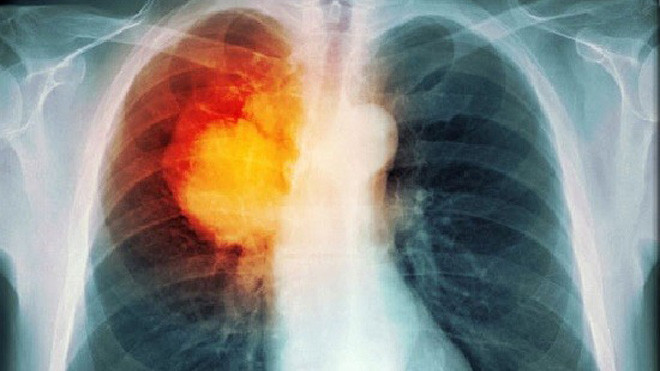

Theo Health Grades, radon là khí phóng xạ tự nhiên không màu, không mùi và là nguyên nhân thứ hai gây ra ung thư phổi, sau thuốc lá. Loại khí này có thể thấm vào nhà từ mặt đất, các vết nứt trên tường hoặc lỗ thông hơi. Khi chúng ta hít phải khí radon, các loại hạt phóng xạ sẽ tích tụ trong phổi, lâu dài sẽ gây ra ung thư.

Theo khảo sát, những người có thân nhân mắc bệnh ung thư phổi sẽ phải đối mặt với nguy cơ mắc căn bệnh này cao gấp đôi so với bình thường. Nếu cha mẹ mang gen đột biến gây ung thư thì con cái có thể sẽ được di truyền gen này.

Đây cũng là nguyên nhân gây ung thư phổi cho những người không hút thuốc. Nếu trong gia đình có người thân hoặc nơi làm việc có người hút thuốc lá, bạn sẽ có nguy cơ cao mắc bệnh ung thư phổi.

Năm 2013, các chuyên gia ung thư của Tổ chức Y tế Thế giới (WHO) đã chính thức tuyên bố tình trạng ô nhiễm không khí là nguyên nhân hàng đầu gây ung thư. Điều đó có thể làm suy yếu hệ hô hấp, gây ra các bệnh phổi mãn tính như viêm phổi, viêm phế quản, nghiêm trọng hơn có thể phát triển thành ung thư.

Trong một số trường hợp, xạ trị cũng có thể gây ra các loại ung thư khác, đặc biệt là ung thư phổi. Nếu bạn đang mắc bệnh, hãy tham khảo ý kiến bác sĩ về lợi ích và rủi ro khi lựa chọn xạ trị để điều trị .

Theo khảo sát, tại khu vực Đông Nam Á và Nam Mỹ, lượng asen cao trong nước giếng lại là yếu tố gây ung thư phổi cho người dân.